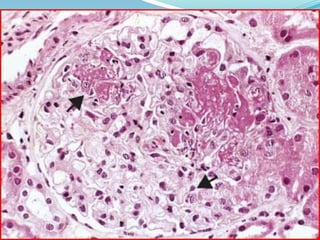

 Kidney-Lupus nephritis affects 50% of SLE patients.

 The principal mechanism of injury is immune

complex deposition in the glomeruli, tubular or

peritubular capillary basement membranes, or larger

blood vessels.

 Five patterns are recognized: minimal mesangial (class

I); mesangial proliferative (class II); focal proliferative

(class III); diffuse proliferative (class IV); and

membranous (class V).

 Kidney-Lupus nephritisaffects 50% of SLE patients.  The principal mechanism of injury is immune complex deposition in the glomeruli, tubular or peritubular capillary basement membranes, or larger blood vessels.  Five patterns are recognized: minimal mesangial (class I); mesangial proliferative (class II); focal proliferative (class III); diffuse proliferative (class IV); and membranous (class V).